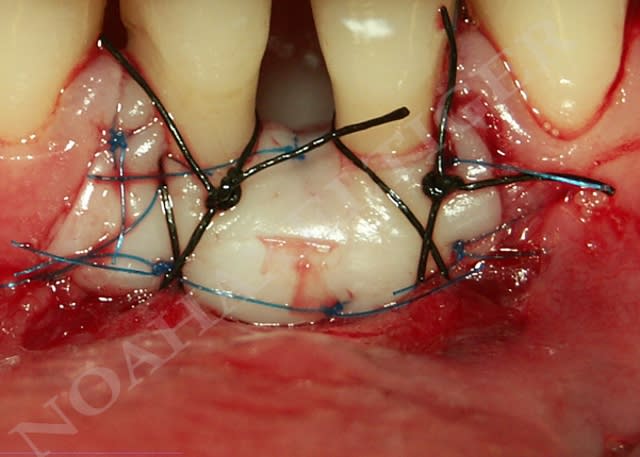

Mise en place du greffon conjonctif ejn6xx - Eugenol

Sutures e7ixmz - Eugenol

Sutures gnghlo - Eugenol

- immobilisation du greffon (cela implique l'utilisation de sutures de facon réfléchie afin de stabiliser et de plaquer ce dernier sur le lit receveur sans le lacérer et le trouer de dix milles trous.)

Le fil est du PROLENE 6/0